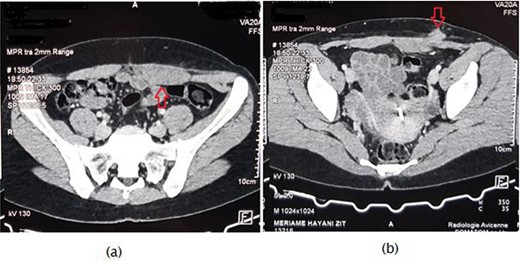

A 31-year-old women, with no history, presents 4 years after a cesarean (incision of Pfannenstiel), two masses one at the level of the left iliac fossa above cesarean scar, and the second one in the lower left rectus muscle gradually increasing in volume, and painful at the time of menstruation. The abdomen examination found an irregular wall tumor of 2 cm, firm, painful, at the level of the left iliac fossa and another of 5 cm in the rectus muscle without cutaneous erythema. An abdominal CT revealed a subcutaneous masse of 2.1 × 1.7 cm in the left iliac fossa and another mass involving the rectus muscle and fascia without traversing the peritoneum (Fig. 1). Elective surgery was performed. During surgery, the two masses were observed, the excision was performed including a 10-mm safety area of each them (Fig. 2). Hemostasis was achieved by ligation of the vascular pedicle entering at the periphery of the mass. Due to a significant defect in the aponeurosis, a polypropylene mesh was used (Fig. 3). Pathology examination confirmed the presence of foci of cystic and hemorrhagic endometriosis (Fig. 4). The postoperative course was uneventful. The patient had a favorable outcome for 2 years without recurrence.

Axial computed tomography scan revealing (a) nodular hypertrophy of the lower left rectus abdominus, (b) mass of 2.1 × 1.7 cm in the left iliac fossa in touch with the rectus muscle.